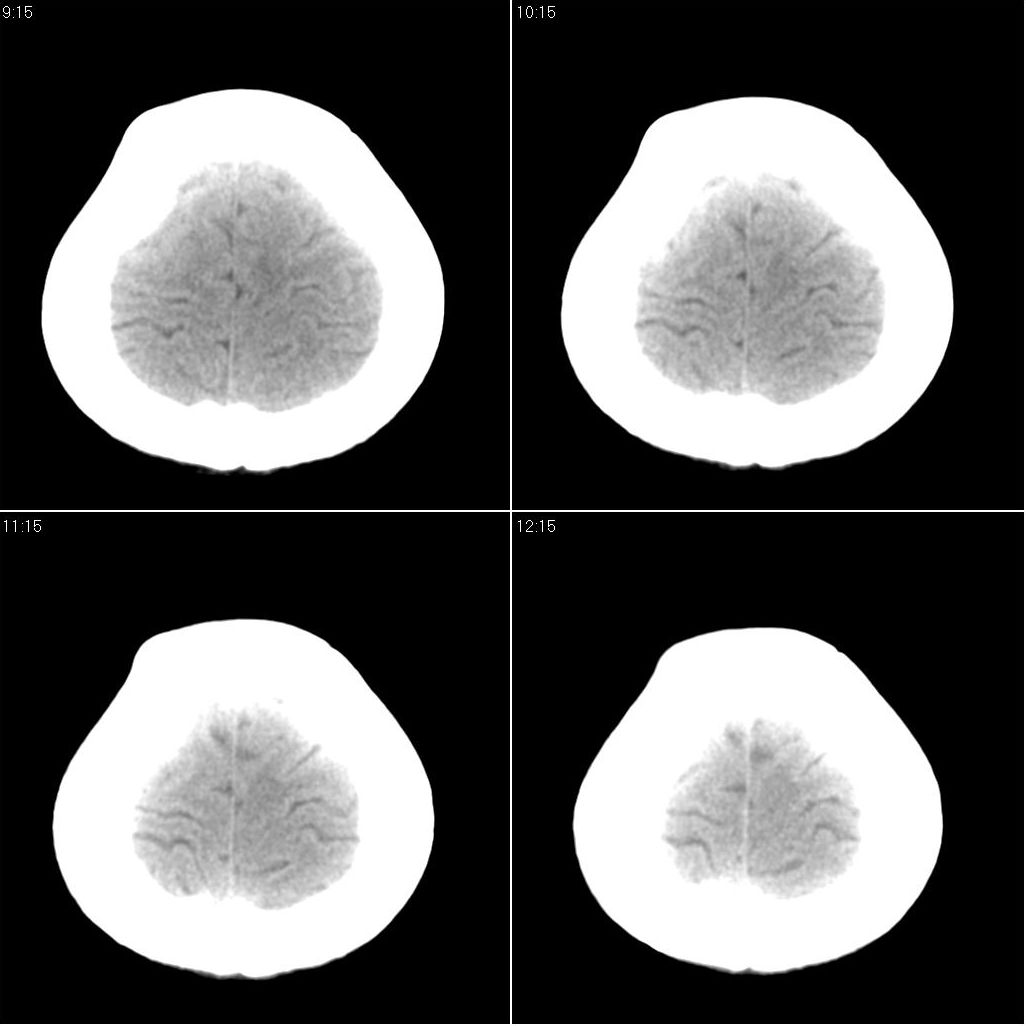

标题: CT16658:女性,49岁。发现右侧额部包块10余年。 [打印本页]

标题: CT16658:女性,49岁。发现右侧额部包块10余年。

支持骨瘤。病史长,病灶与颅骨密度一致,周围软组织没有异常改变。

右额部颅骨外板为主向外突出局限致密骨影,密度均匀,考虑额骨致密骨瘤

右侧额骨致密骨瘤。

考虑右侧额骨致密骨瘤。